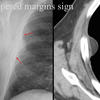

Tapered margins sign

Pleural or extrapleural origin

Date: 04/28/2014

Views: 5238